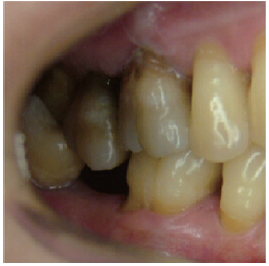

平面-平面接觸

這是一種牙(牙合)面溝窩結(jié)構(gòu)基本消失的咬合狀態(tài),常見的異常表現(xiàn)是上、下后牙因?qū)θ嘘P(guān)系而磨成平面(牙合)。平面型(牙合)接觸(圖4)失去了牙尖斜面對(duì)咬合力的分解作用以及對(duì)咬合運(yùn)動(dòng)的引導(dǎo)作用,對(duì)食物失去了穿透作用和研磨作用,咀嚼模式以垂直壓榨為主。考慮到后牙在牙槽骨中的植根方向或多或少有近、遠(yuǎn)中向或頰、舌向的傾斜,平面(牙合)的牙(牙合)面罕有與牙長(zhǎng)軸方向正好垂直的情況(圖5),因此當(dāng)平面(牙合)的整個(gè)牙面共同承擔(dān)咬合力時(shí),其所承受的咬合力方向與牙長(zhǎng)軸方向構(gòu)成一定的角度,而不利于牙或牙周組織的健康。

圖4 平面(牙合)